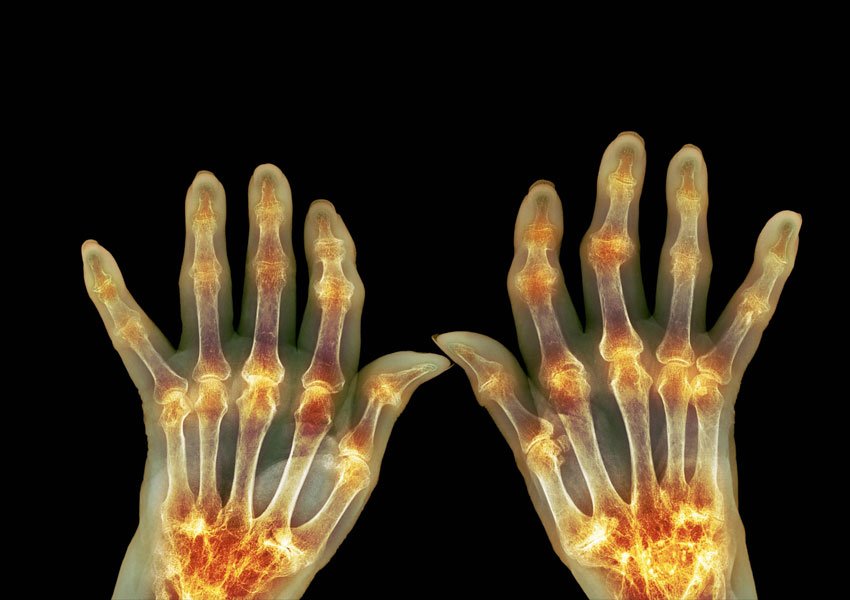

Best Ayurvedic Treatments for Joint Pain and Arthritis Relief

For joint pain and arthritis relief, Ayurvedic treatments focus on restoring balance in your body. You can incorporate key herbs like turmeric and ginger, known for their anti-inflammatory properties. A balanced diet rich in omega-3s and antioxidants is essential. Gentle exercises, meditation, and warm oil massages can enhance your well-being. By understanding your unique constitution, […]

Top Ayurvedic Remedies for Managing Arthritis Pain in Cold Weather

When cold weather exacerbates arthritis pain, consider Ayurvedic treatment for arthritis in Bangalore for a holistic approach. Warm Ayurvedic massage therapy eases pain, boosts circulation, and relaxes muscles. Anti-Inflammatory Herbal Teas soothe inflammation, aid digestion, and support immunity. Turmeric paste, rich in curcumin, reduces joint inflammation and enhances flexibility. Engage in Yoga and Gentle Stretching Exercises […]

Best Ayurvedic Treatments for Arthritis: Relieving Joint Pain Naturally

Explore the ancient wisdom of Ayurveda for relieving joint pain naturally. Embrace an Ayurvedic diet rich in warming spices like turmeric and ginger. Incorporate herbal remedies such as turmeric, ashwagandha, and ginger to combat inflammation. Experience the soothing benefits of Abhyanga, an Ayurvedic oil massage that enhances circulation and flexibility. Discover Panchakarma treatment in Bangalore, […]

Protecting Your Joints: Ayurvedic Care for Arthritis in Monsoon

Monsoon Challenges for Arthritis Patients Arthritis patients often face increased discomfort and challenges during the monsoon season due to fluctuating weather conditions and high humidity levels. The impact of the monsoon weather on arthritis can be significant, with many patients experiencing heightened joint pain, stiffness, and inflammation. It is vital for individuals with arthritis to […]

Ayurvedic Guide to Manage Joint Health

1. Ayurvedic Principles for Joint Health To effectively manage joint health, you can begin by incorporating Ayurvedic principles into your daily routine. Ayurveda, an ancient holistic healing system, offers various natural remedies and therapies that can help alleviate joint pain and inflammation. One such remedy is the use of Ayurvedic oils for joint massage. These […]